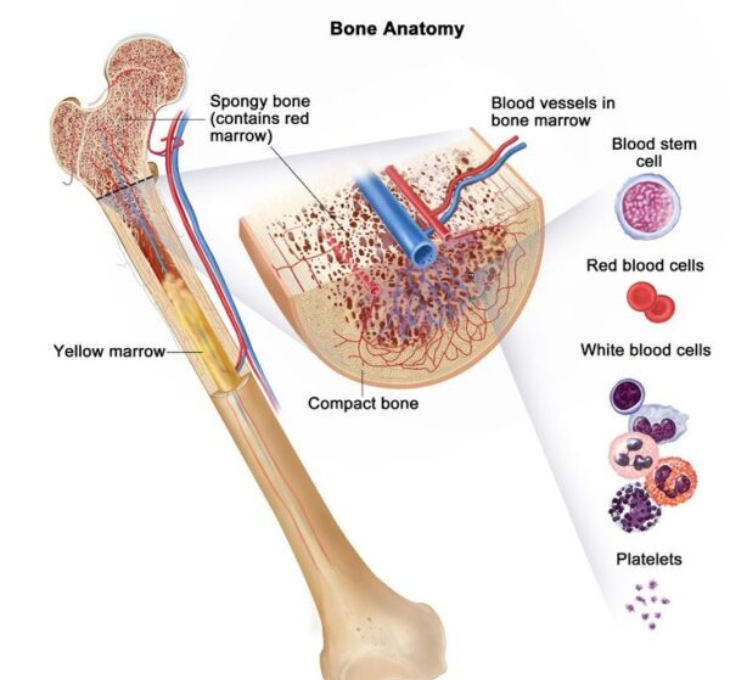

Bone Scan

Detects bone cancer, tumors, fractures, or infections. No special preparations are required.